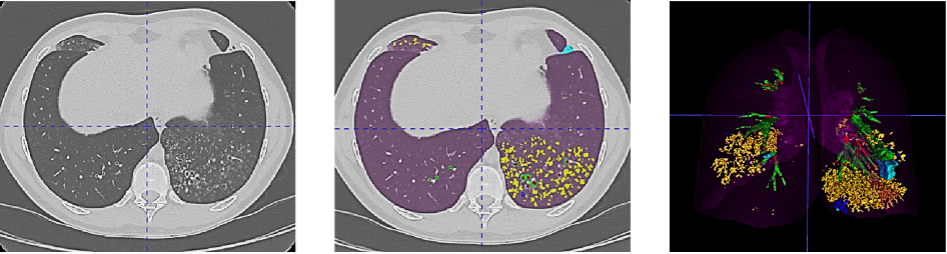

Figure 1. Example of the Normalized Volume of Airway Abnormalities (NOVAA) method. On the left, native CT scan; in the center, AI-automatically labeled CT scan; and on the right, 3D volumetric reconstruction of structural abnormalities. Artificial intelligence enables recognition and semantic segmentation of key structural alterations in airway diseases, such as bronchial dilations (in red), wall thickening (in green), bronchial mucus (in blue), and bronchiolar mucus (in yellow).